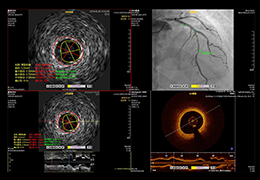

ANYTHINK 经导管主动脉瓣膜置换术分析系统